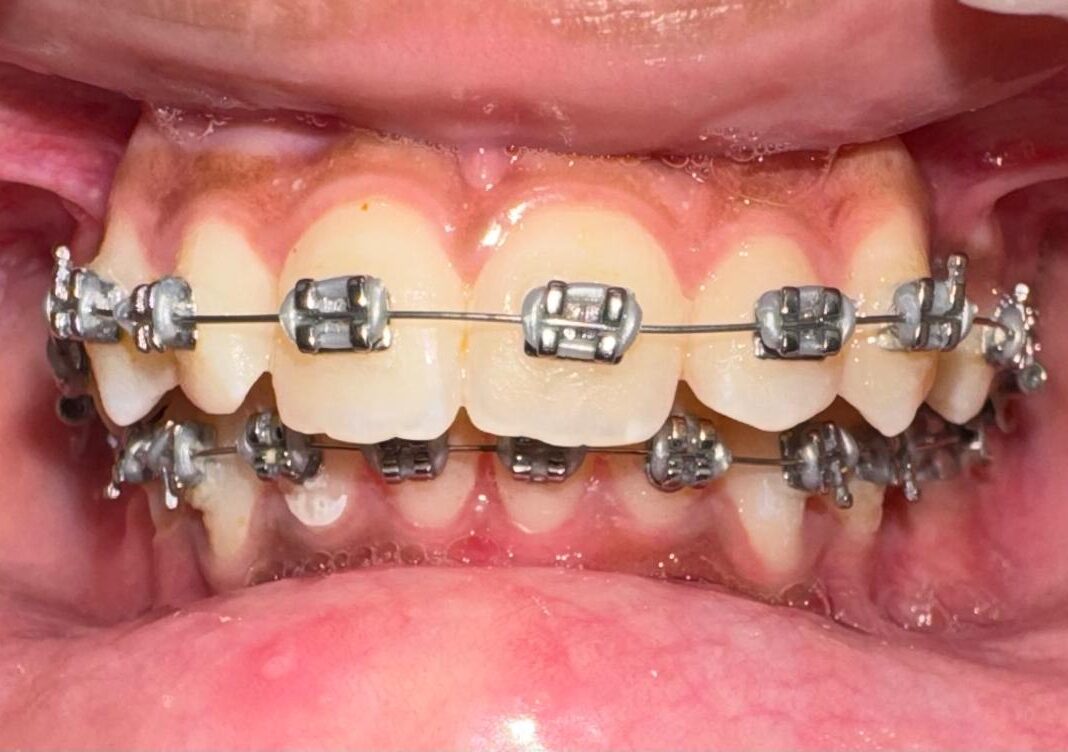

Teeth braces are orthodontic devices consisting of brackets, wires, and bands that apply gentle pressure to...